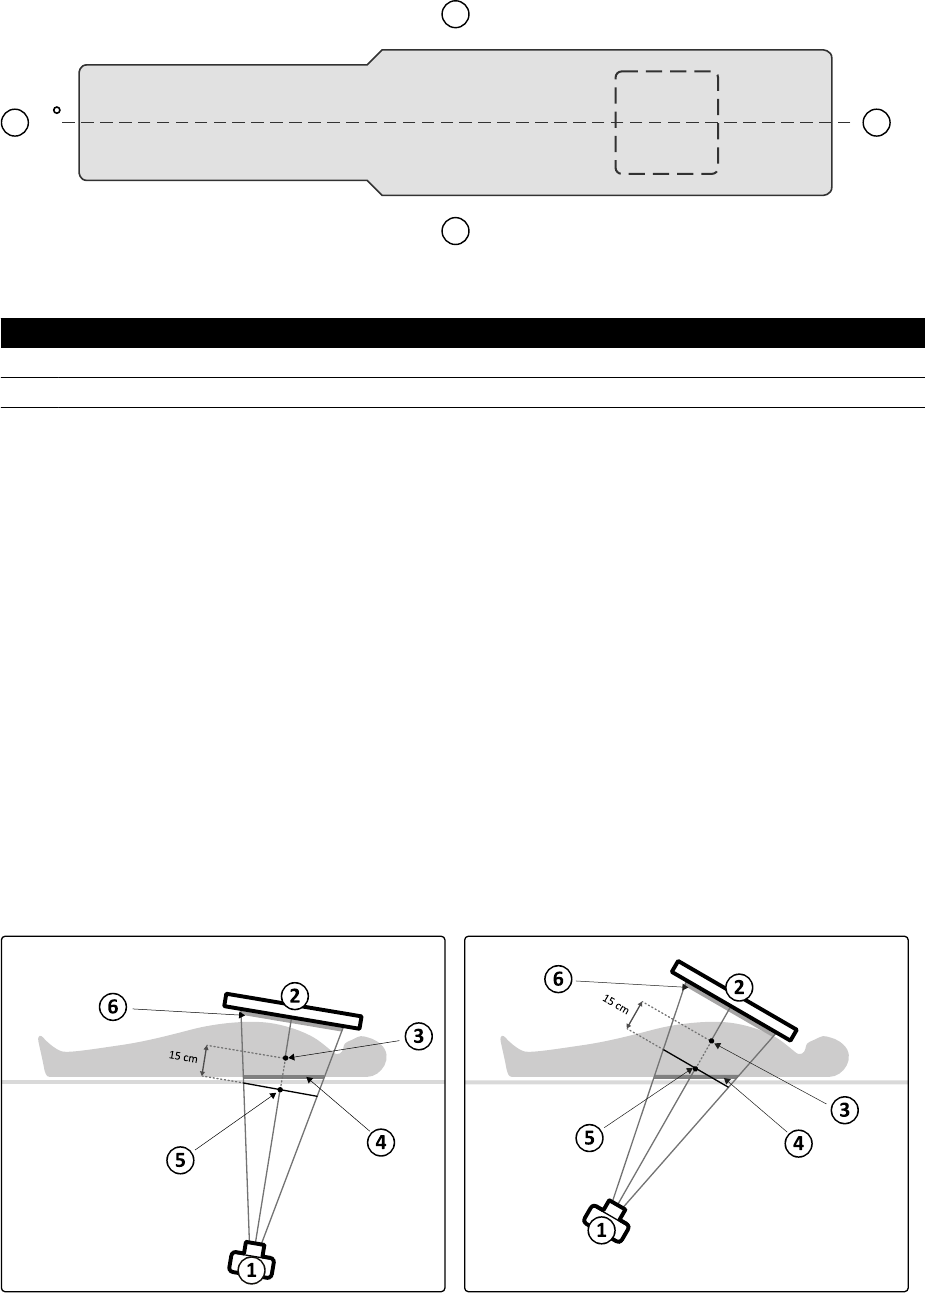

16.13.1 Narzędzie laserowe XperGuide............................................................................ 286

11.17 Narzędzie laserowe XperGuide (opcja)................................................................................ 203

11.17.1 Włączanie i wyłączanie narzędzia laserowego XperGuide................................... 204

11.17.2 Ładowanie narzędzia laserowego XperGuide...................................................... 205